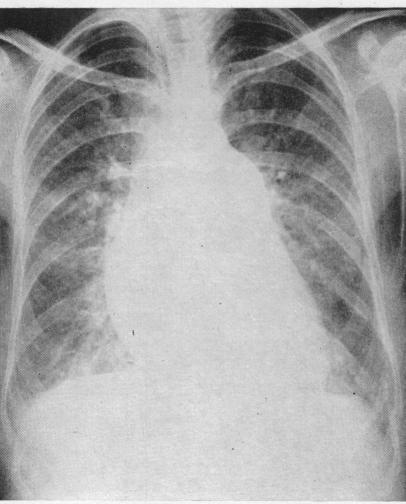

Pulmonary hypertension in mitral stenosis.

Br Heart J. 1957 Oct;19(4):457-72. doi: 10.1136/hrt.19.4.457.